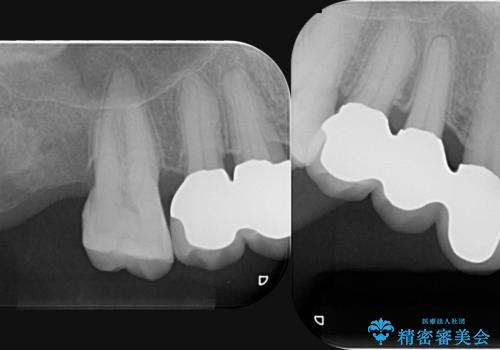

部分矯正を含む 歯周病治療 (再生治療・歯周ポケット除去・MTM・連結補綴)

- 75万円(仮歯・メタルボンドクラウン×3・再生療法・小矯正・歯周ポケット除去手術)費用は治療当時の料金となります

今回連結補綴を行うにあたり、歯周病の問題を解決するために再生療法・歯周ポケット除去手術を、またより歯の神経を保存し力に対抗できる環境を整えるために小矯正を行い精度の高いメタルボンドクラウンを製作することができました。